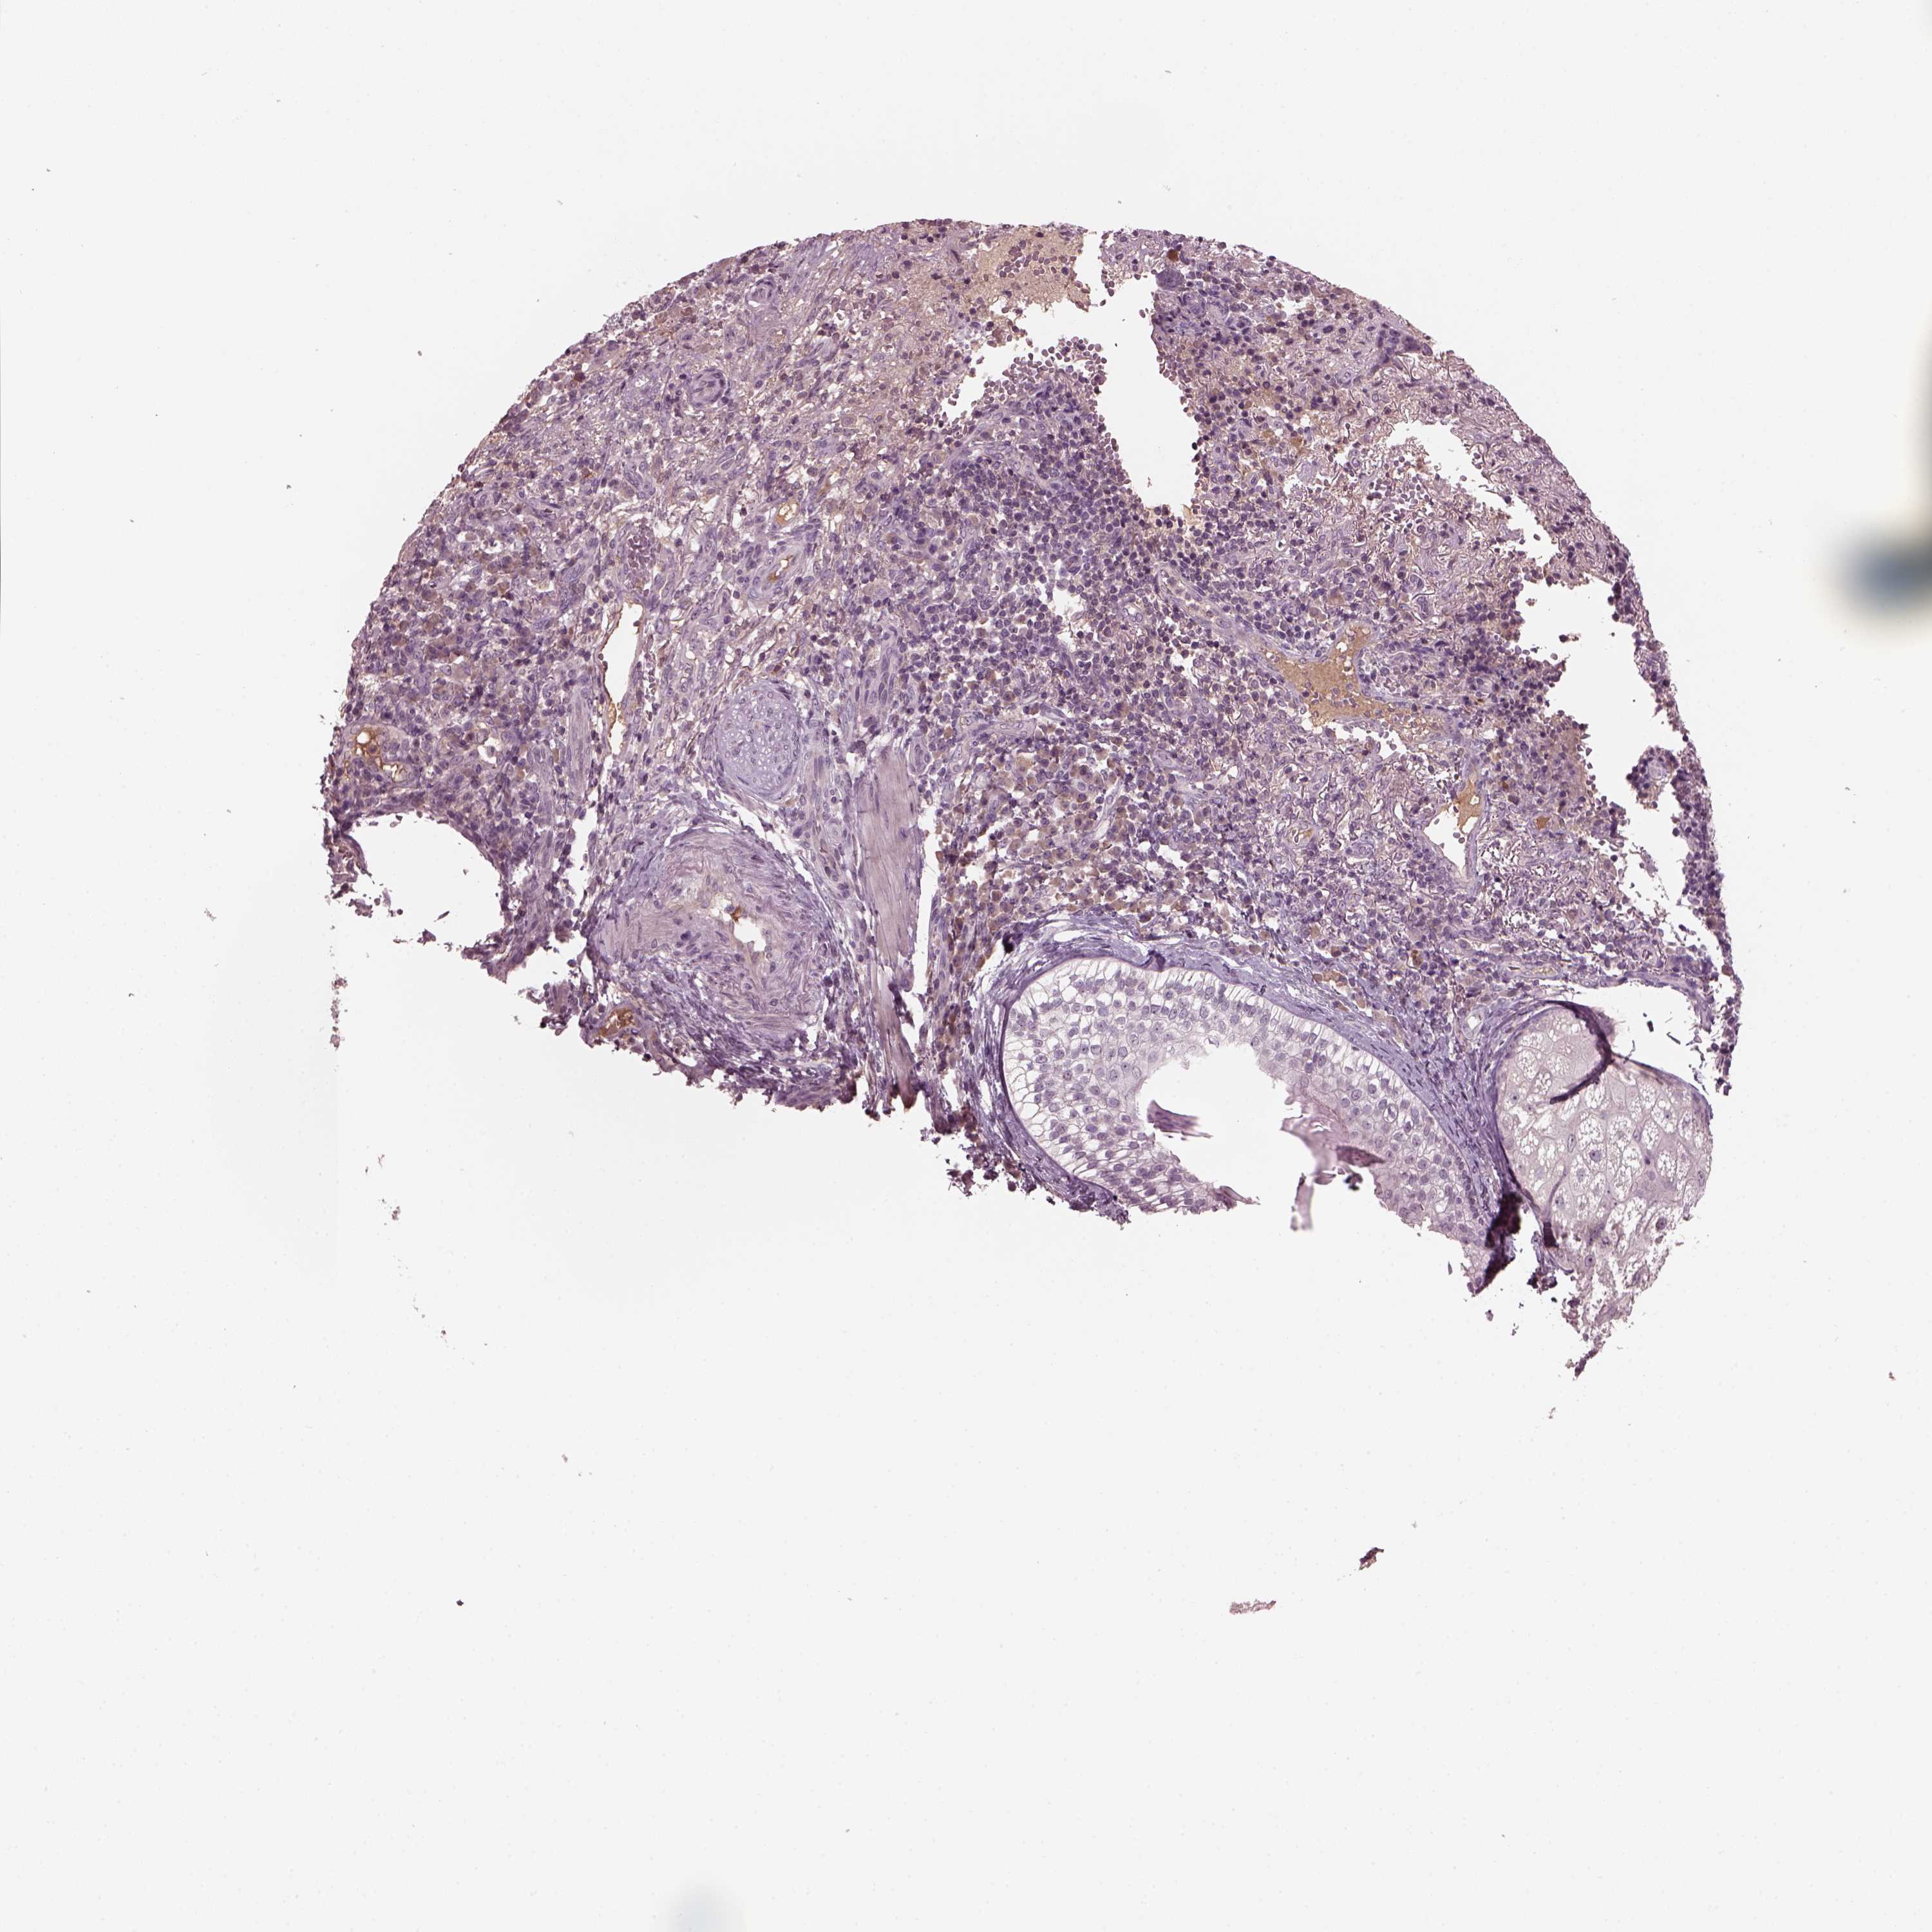

CANCER SKIN CANCER Show tissue menu

Basal cell and squamous cell cancer

SKIN CANCER - Protein expressioni

A mouse-over function shows sample information and annotation data. Click on an image to view it in a full screen mode. Samples can be filtered based on level of antibody staining by selecting one or several of the following categories: high, medium, low and not detected. The assay and annotation is described here.

Each image is clickable and will lead to virtual microscopy that enables deeper exploration of all samples and also displays staining intensity scores, fraction scores and subcellular localization as well as patient and tissue information for each sample.

Antibody HPA058413

Staining

High

Medium

Low

Not detected

Intensity

Strong

Moderate

Weak

Negative

Quantity

>75%

75%-25%

<25%

None

Location

Nuclear

Cytoplasmic/membranous

Cytoplasmic/membranous,nuclear

Basal cell carcinoma

Squamous cell carcinoma, NOS